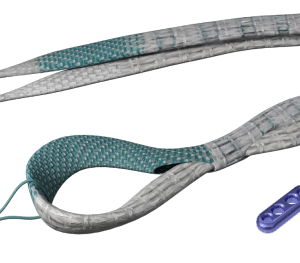

Gân nhân tạo tái tạo dây chằng Poly-Tape các cỡ

Dùng trong phẫu thuật tái tạo gân cơ tứ đầu đùi, gân bánh chè, MPFL, … Cung cấp độ bền nội tại tuyệt vời và giúp việc phục hồi chức năng vận động diễn ra sớm hơn. Cấu trúc: Băng dệt hở với các đoạn dệt dày, thuôn thành sợi ở mỗi đầu. Cấu trúc này cho phép mô tự nhiên phát triển tích hợp vào trong thiết bị.

Tiêu chuẩn: CE, ISO